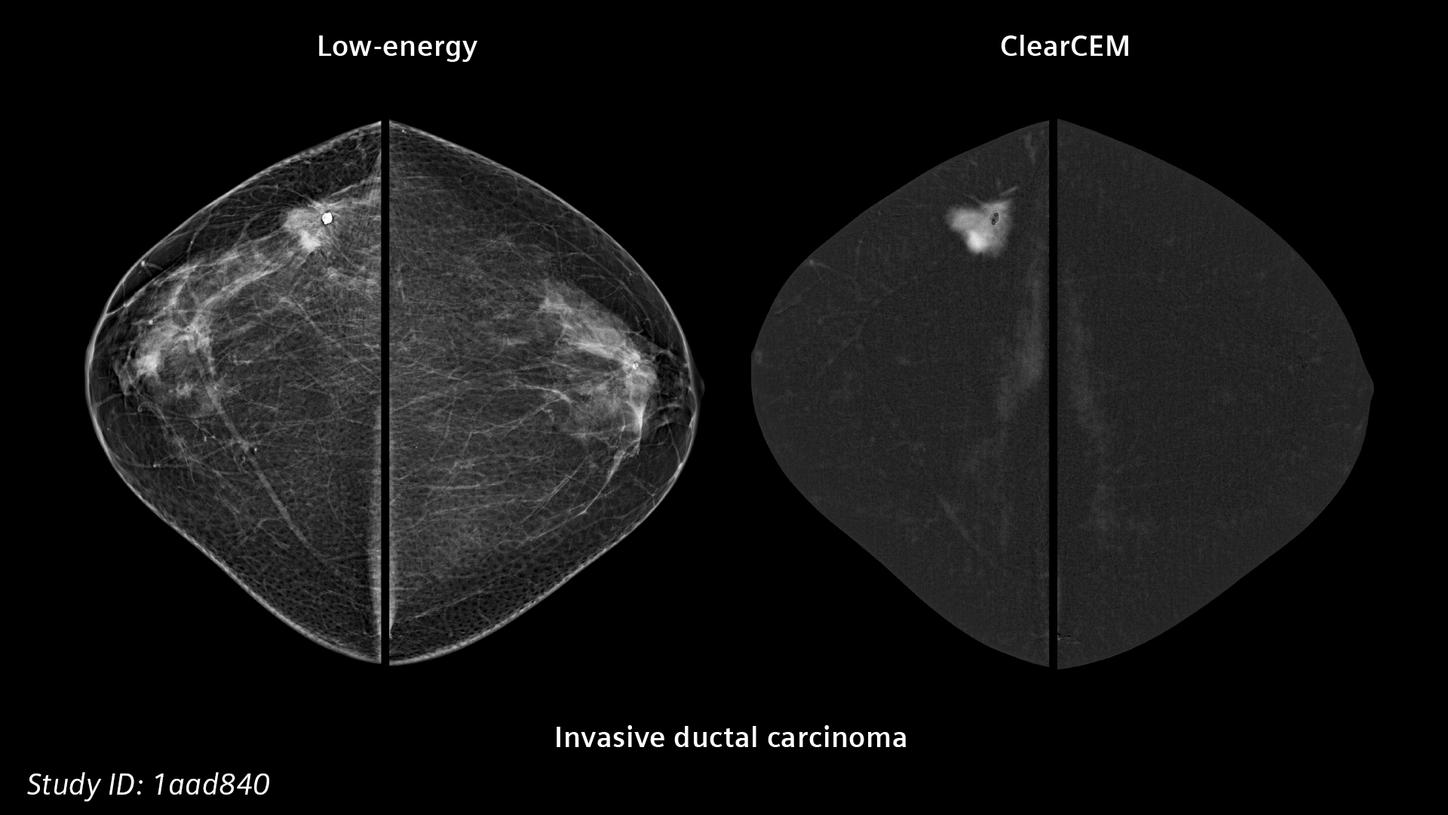

- ClearCEM, exceptional contrast-enhanced image quality for diagnostic confidence, now also available for biopsy

A new era in contrast-enhanced digital mammography

ClearCEM delivers outstanding image quality1, and may even serve as an alternative to MRI6.

ClearCEM:

A new era in contrast-enhanced mammogrpahy

Our advanced, proprietary algorithm delivers outstanding image quality8, bringing mammography closer to MRI.